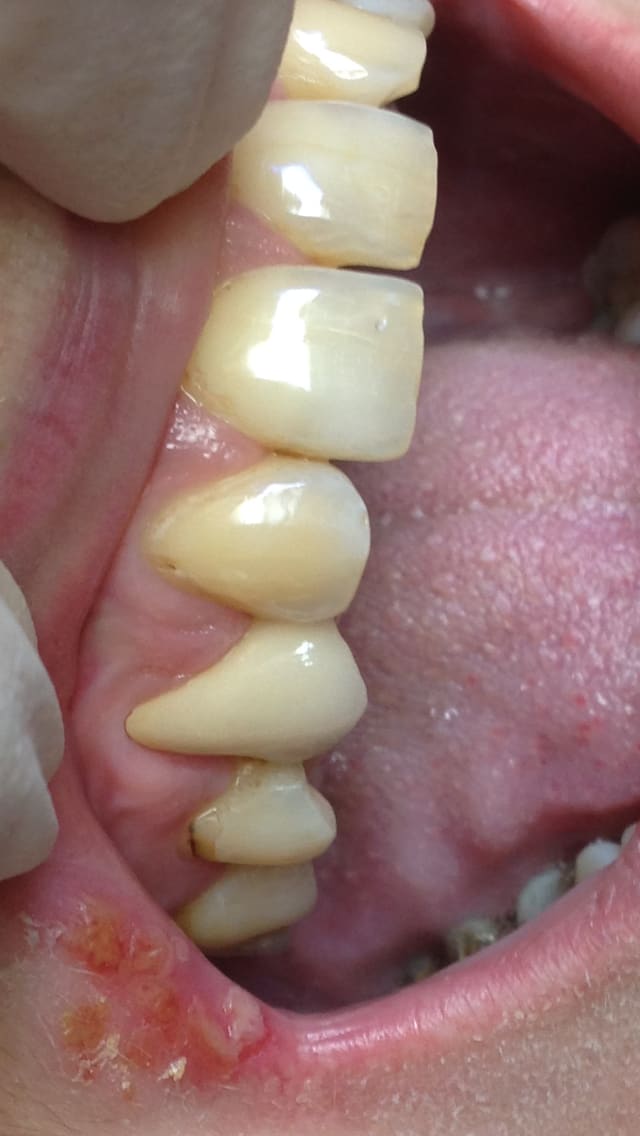

là ,on est à la 2eme seance ,apres la 1ere seance de taille rapidos et avant empreinte .

regardes bien les limites ,elles on l'air bien placées ,non ?